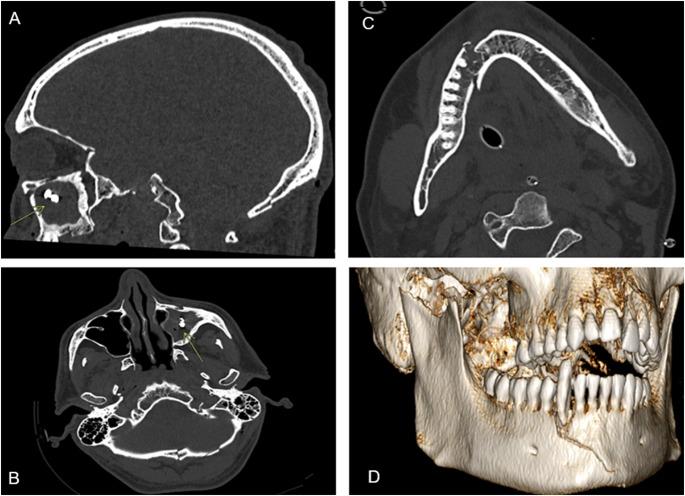

This retrospective study included 611 patients who underwent TBCT following high-energy trauma between July 2024 and February 2025. DTMI findings were analyzed based on initial radiology reports and retrospective image review.

DTMI was identified in 124 of 611 patients (20.2%), of which only 76 cases (61%) were reported at admission. Dental trauma was significantly underreported (76% missed rate), with only 12 of 50 cases (24%) initially recognized. In contrast, maxillofacial injuries were detected in 75 of 97 cases (77,3%). Most DTMI-positive patients (82/124, 66%) had additional traumatic findings, including cranial or spinal injuries (33/124, 26.6%) and multi-district trauma (29/124, 23.4%). Only 20 patients (16%) presented with isolated facial trauma. A small subgroup (18/124, 14.5%) had DTMI with no other traumatic findings, suggesting possible oversight in the absence of overt injury. Underreporting rates were slightly higher during night shifts (55%) compared to daytime (48%), though not statistically significant (χ² = 0.654, p > 0.05). DTMI was more common in males (ratio 1.79:1).

611例患者中有124例(20.2%)被诊断为DTMI,其中入院时仅报告了76例(61%)。牙外伤的漏报率显著(漏报率76%),50例中仅12例(24%)最初被识别。相比之下,97例中的75例(77.3%)被检测出颌面损伤。大多数DTMI阳性患者(82/124,66%)有其他创伤性发现,包括颅脑或脊柱损伤(33/124,26.6%)和多部位创伤(29/124,23.4%)。仅有20例患者(16%)表现为孤立性面部创伤。一小部分亚组(18/124,14.5%)有DTMI但无其他创伤性发现,提示在无明显损伤时可能存在漏诊。夜班期间的漏报率(55%)略高于白班(48%),但差异无统计学意义(χ² = 0.654,p>0.05)。DTMI在男性中更常见(比例为1.79:1)。